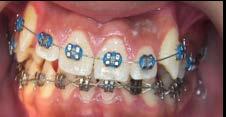

Adherencia a las indicaciones del tratamiento ortodóntico en pacientes con aparatología fija

La adherencia al tratamiento se define como el grado de comportamiento de una persona para seguir las recomendaciones sugeridas por el prestador de servicios de salud, en este caso, el ortodoncista. La adolescencia se considera una etapa idónea para recibir tratamiento de ortodoncia, ya que durante este periodo se presentan cambios fisiológicos, estructurales y anatómicos relacionados con el crecimiento y desarrollo de la cara y de las arcadas dentarias; sin embargo, uno de los principales retos es lograr y mantener una adecuada conexión con el paciente para obtener resultados favorables en la mejora de su oclusión. Objetivo: Evaluar el nivel de adherencia al tratamiento con aparatología fija en pacientes adolescentes del Instituto Bioprogresivo de Ortodoncia. Metodología: Estudio transversal con muestreo por conveniencia. Se evaluó el nivel de adherencia al tratamiento en pacientes atendidos en el Instituto mediante un cuestionario validado de autorreporte, aplicado durante los meses de agosto a diciembre de 2024. Se realizó un análisis descriptivo de la muestra y posteriormente se evaluó la frecuencia de reporte de los ítems. Resultados: El 81.7% de la muestra reportó haber recibido indicaciones higiénicas; el 85.3% recordó las instrucciones dietéticas recibidas; el 96.4% acudió a sus citas en la fecha y hora convenidas; el 97.5% refirió dar seguimiento a su tratamiento, aun cuando ya se sentían satisfechos con los resultados; el 92.6% solicitó consulta inmediata cuando se desprendió algún bracket; el 96.4% siguió las indicaciones incluso al salir de viaje; el 91.5% consultó oportunamente al ortodoncista ante la presencia de alguna molestia; el 92.6% recordó las fechas de sus próximas consultas, y solo el 2.5% reportó haber tenido conflictos con su ortodoncista. Conclusión: La adherencia de los pacientes al tratamiento de ortodoncia en la muestra fue adecuada; no obstante, es importante evaluar de forma constante este aspecto para verificar la motivación del paciente adolescente, evitar la deserción prematura del tratamiento y prevenir posibles complicaciones.

Palabras clave: adherencia, adolescentes, indicaciones, ortodoncia.

Las maloclusiones son consideradas un importante problema de salud pública. De acuerdo con la Organización Mundial de la Salud (OMS), estas constituyen el tercer problema de salud bucal más relevante, después de la caries dental y las enfermedades periodontales.1 Se estima que, en México, alrededor del 60% de la población presenta alguna de estas condiciones.2 Las maloclusiones son alteraciones en la posición de los componentes dentales o esqueletales del sistema estomatognático.3 Su efecto no es solo funcional y/o estético, sino que también influye en los aspectos psicosociales y en la calidad de vida de quienes las padecen.4

De acuerdo con la OMS, la adolescencia es el periodo comprendido entre los 10 y 19 años; en esta etapa se producen cambios físicos, psicológicos, biológicos, intelectuales y sociales que corresponden a la transición de la infancia al estado adulto.5 El abordaje de las maloclusiones se lleva a cabo mediante el tratamiento ortodóntico, en el cual se emplean distintos aditamentos con la finalidad de armonizar la oclusión y los rasgos faciales del tercio medio e inferior del rostro.6 La adolescencia es el momento preferido para realizar este tratamiento, ya que durante esta etapa la dentición permanente ha erupcionado, pero el crecimiento craneofacial aún puede aprovecharse.7

Para que el tratamiento ortodóntico sea exitoso, se requiere la cooperación del paciente en factores tales

como asistir a las citas, mantener una adecuada higiene oral, seguir las recomendaciones dietéticas, así como usar y cuidar los aparatos y aditamentos prescritos.8 Sin embargo, el tratamiento puede alterar las rutinas establecidas e interferir con las actividades sociales del paciente adolescente, además de repercutir en su autoestima debido a su aspecto físico. Por ello, resulta imperativo mantener una comunicación adecuada que permita comprender las necesidades y expectativas del paciente respecto al tratamiento y generar en este una adherencia adecuada a las indicaciones prescritas por parte del ortodoncista, a fin de favorecer el éxito del tratamiento.9

Resultados

Descripción de la muestra

En el estudio participaron 82 adolescentes; el 60.9% (n = 50) fueron mujeres, quienes presentaron una edad promedio de 15.3 ± 2.5 años. El 78.1% (n = 64) refirió que era la primera vez que se encontraba bajo tratamiento ortodóntico.

Adherencia al tratamiento

De acuerdo con la encuesta de adherencia en pacientes adolescentes bajo tratamiento ortodóntico, el 81.7% de la muestra reportó haber recibido

indicaciones higiénicas; el 85.3% recordó las instrucciones dietéticas recibidas; el 96.4% acudió a sus citas en la fecha y hora convenidas; el 97.5% refirió dar seguimiento a su tratamiento, aun cuando ya se sentían satisfechos con los resultados; el 92.6% solicitó consulta inmediata cuando se desprendió algún bracket; el 96.4% siguió las indicaciones incluso cuando salieron de viaje; el 91.5% consultó de manera oportuna al ortodoncista ante la presencia de alguna molestia; el 92.6% recordó las fechas de sus próximas consultas y solo el 2.5% reportó haber tenido conflictos con su ortodoncista (Tabla 2).